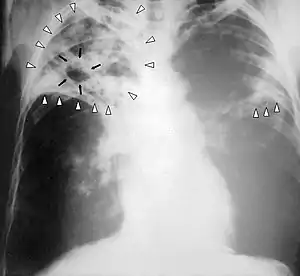

| رادیوگرافی قفسه سینه شخص مبتلا به بیماری سل پیشرفته. عفونت در هر دو سمت ریه با پیکانهای سفید نمایش داده شده و تشکیل حفره سلی با پیکانهای مشکی مشخص شدهاست. | |